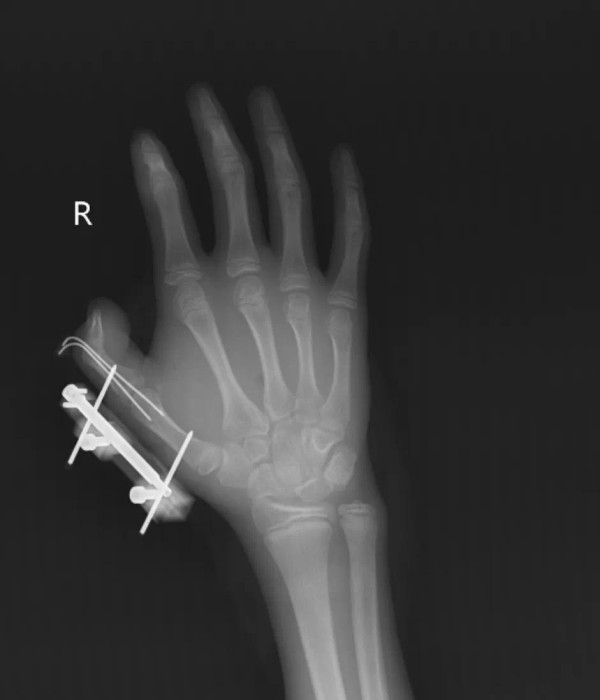

據悉,這名14歲少年維維(化名)從爸爸網購雪糕的包裹中發現了乾冰,便出於好奇,將其當成玩具拿在手裏反覆搖晃。沒想到,密封袋內的乾冰突然發生爆炸,維維的右手瞬間鮮血直流。他的拇指虎口處被撕開一道長約10厘米的傷口,深可見骨,肌肉組織斷裂外露,並伴隨拇指骨折、關節脫位,整個拇指完全失去知覺。

家人見狀立即將他送醫,醫生連夜進行清創、復位和修復手術。儘管維維的拇指最終保住了,但後續仍需進行長期的康復訓練,才能慢慢恢復手部功能。維維事後懊悔不已:「早知道乾冰這麼危險,我絕對不會去玩。」